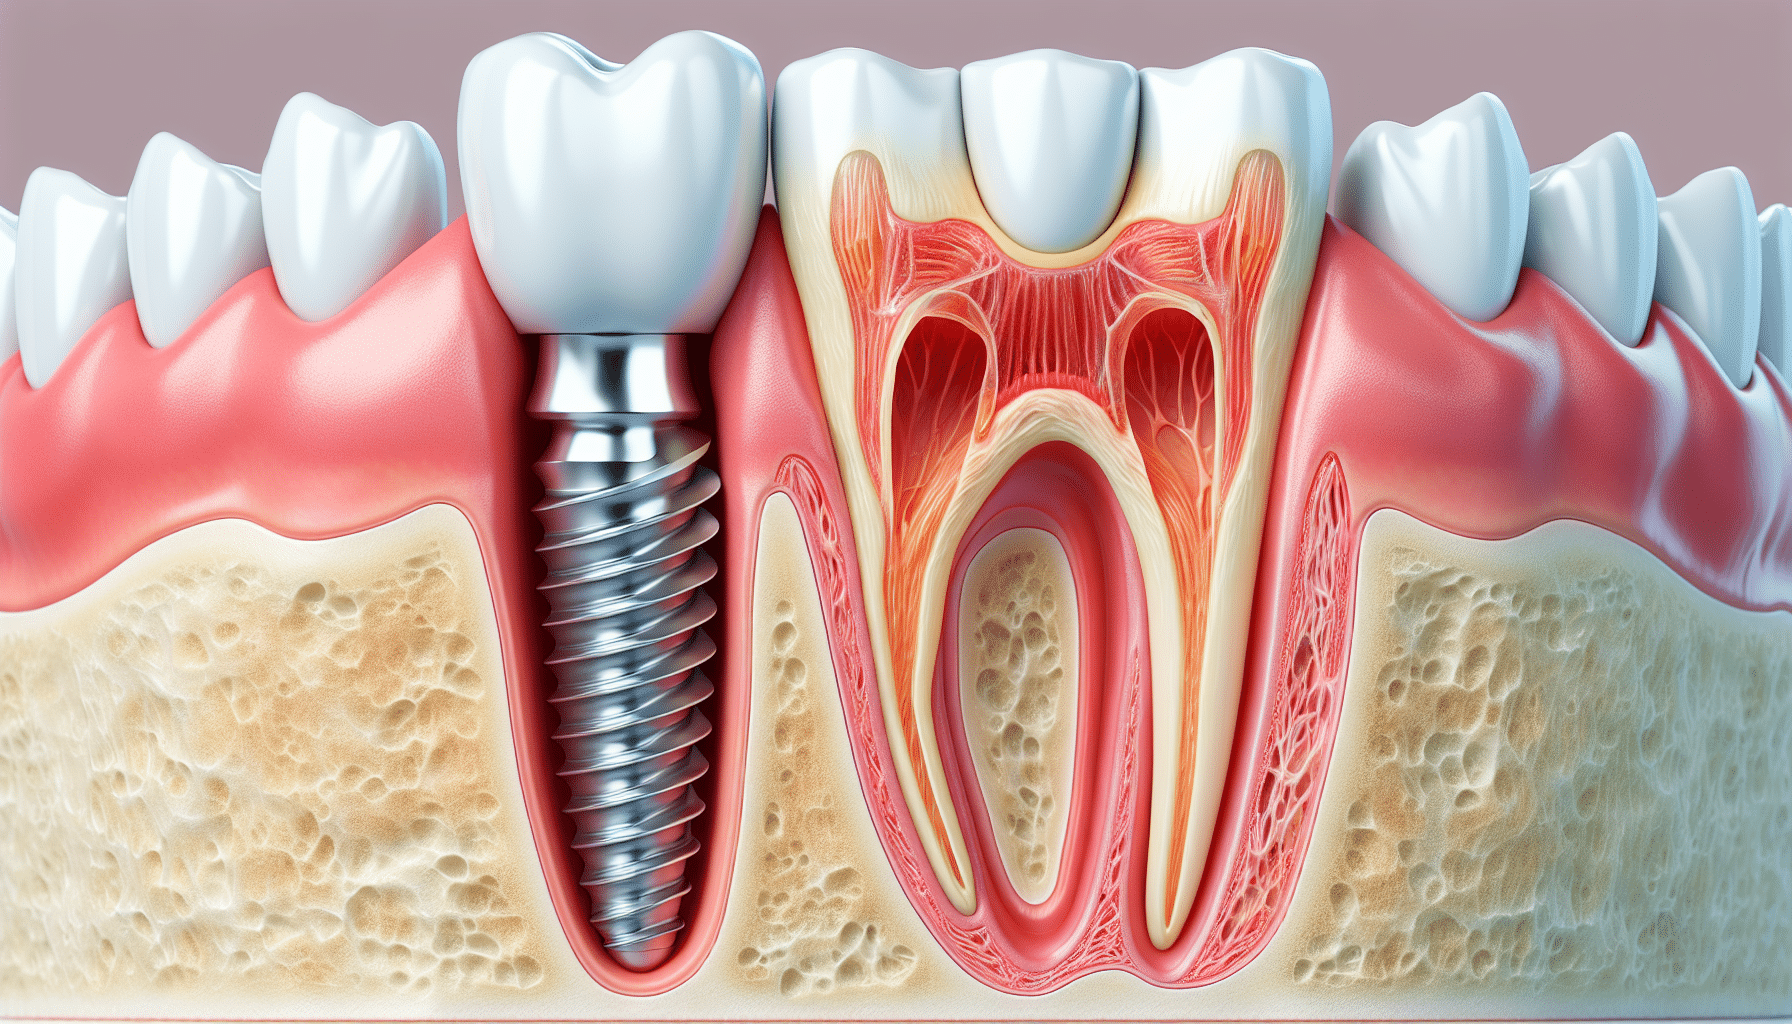

Dental implants are designed to function as a permanent solution for tooth loss. They consist of a titanium post surgically placed into the jawbone, which serves as an artificial tooth root. Once healed, a crown is attached to the implant, completing the restoration. Implants provide stability that bridges and dentures cannot, offering a reliable and aesthetic alternative. They integrate with the jawbone naturally, preventing bone loss and supporting facial structure.

The journey to a fully restored tooth involves several stages. Initially, a comprehensive examination ensures the patient is a suitable candidate. Imaging and assessments of bone density guide the planning phase. The surgical placement of the implant follows, during which precision is key to achieving optimal integration with the jawbone. Healing time allows the implant to fuse securely, a process known as osseointegration. Once healed, an abutment is connected to the implant, and the final crown is attached, restoring function and aesthetics.

The surgical procedure itself is precise yet minimally invasive. Post-surgery, patients experience a period of healing where the jawbone integrates with the implant. During this time, maintaining oral hygiene and following recommended guidelines ensures the best results. Recovery experiences vary, but most individuals can resume daily activities with minimal disruption. Regular check-ups allow professionals to monitor healing and progress throughout the process.